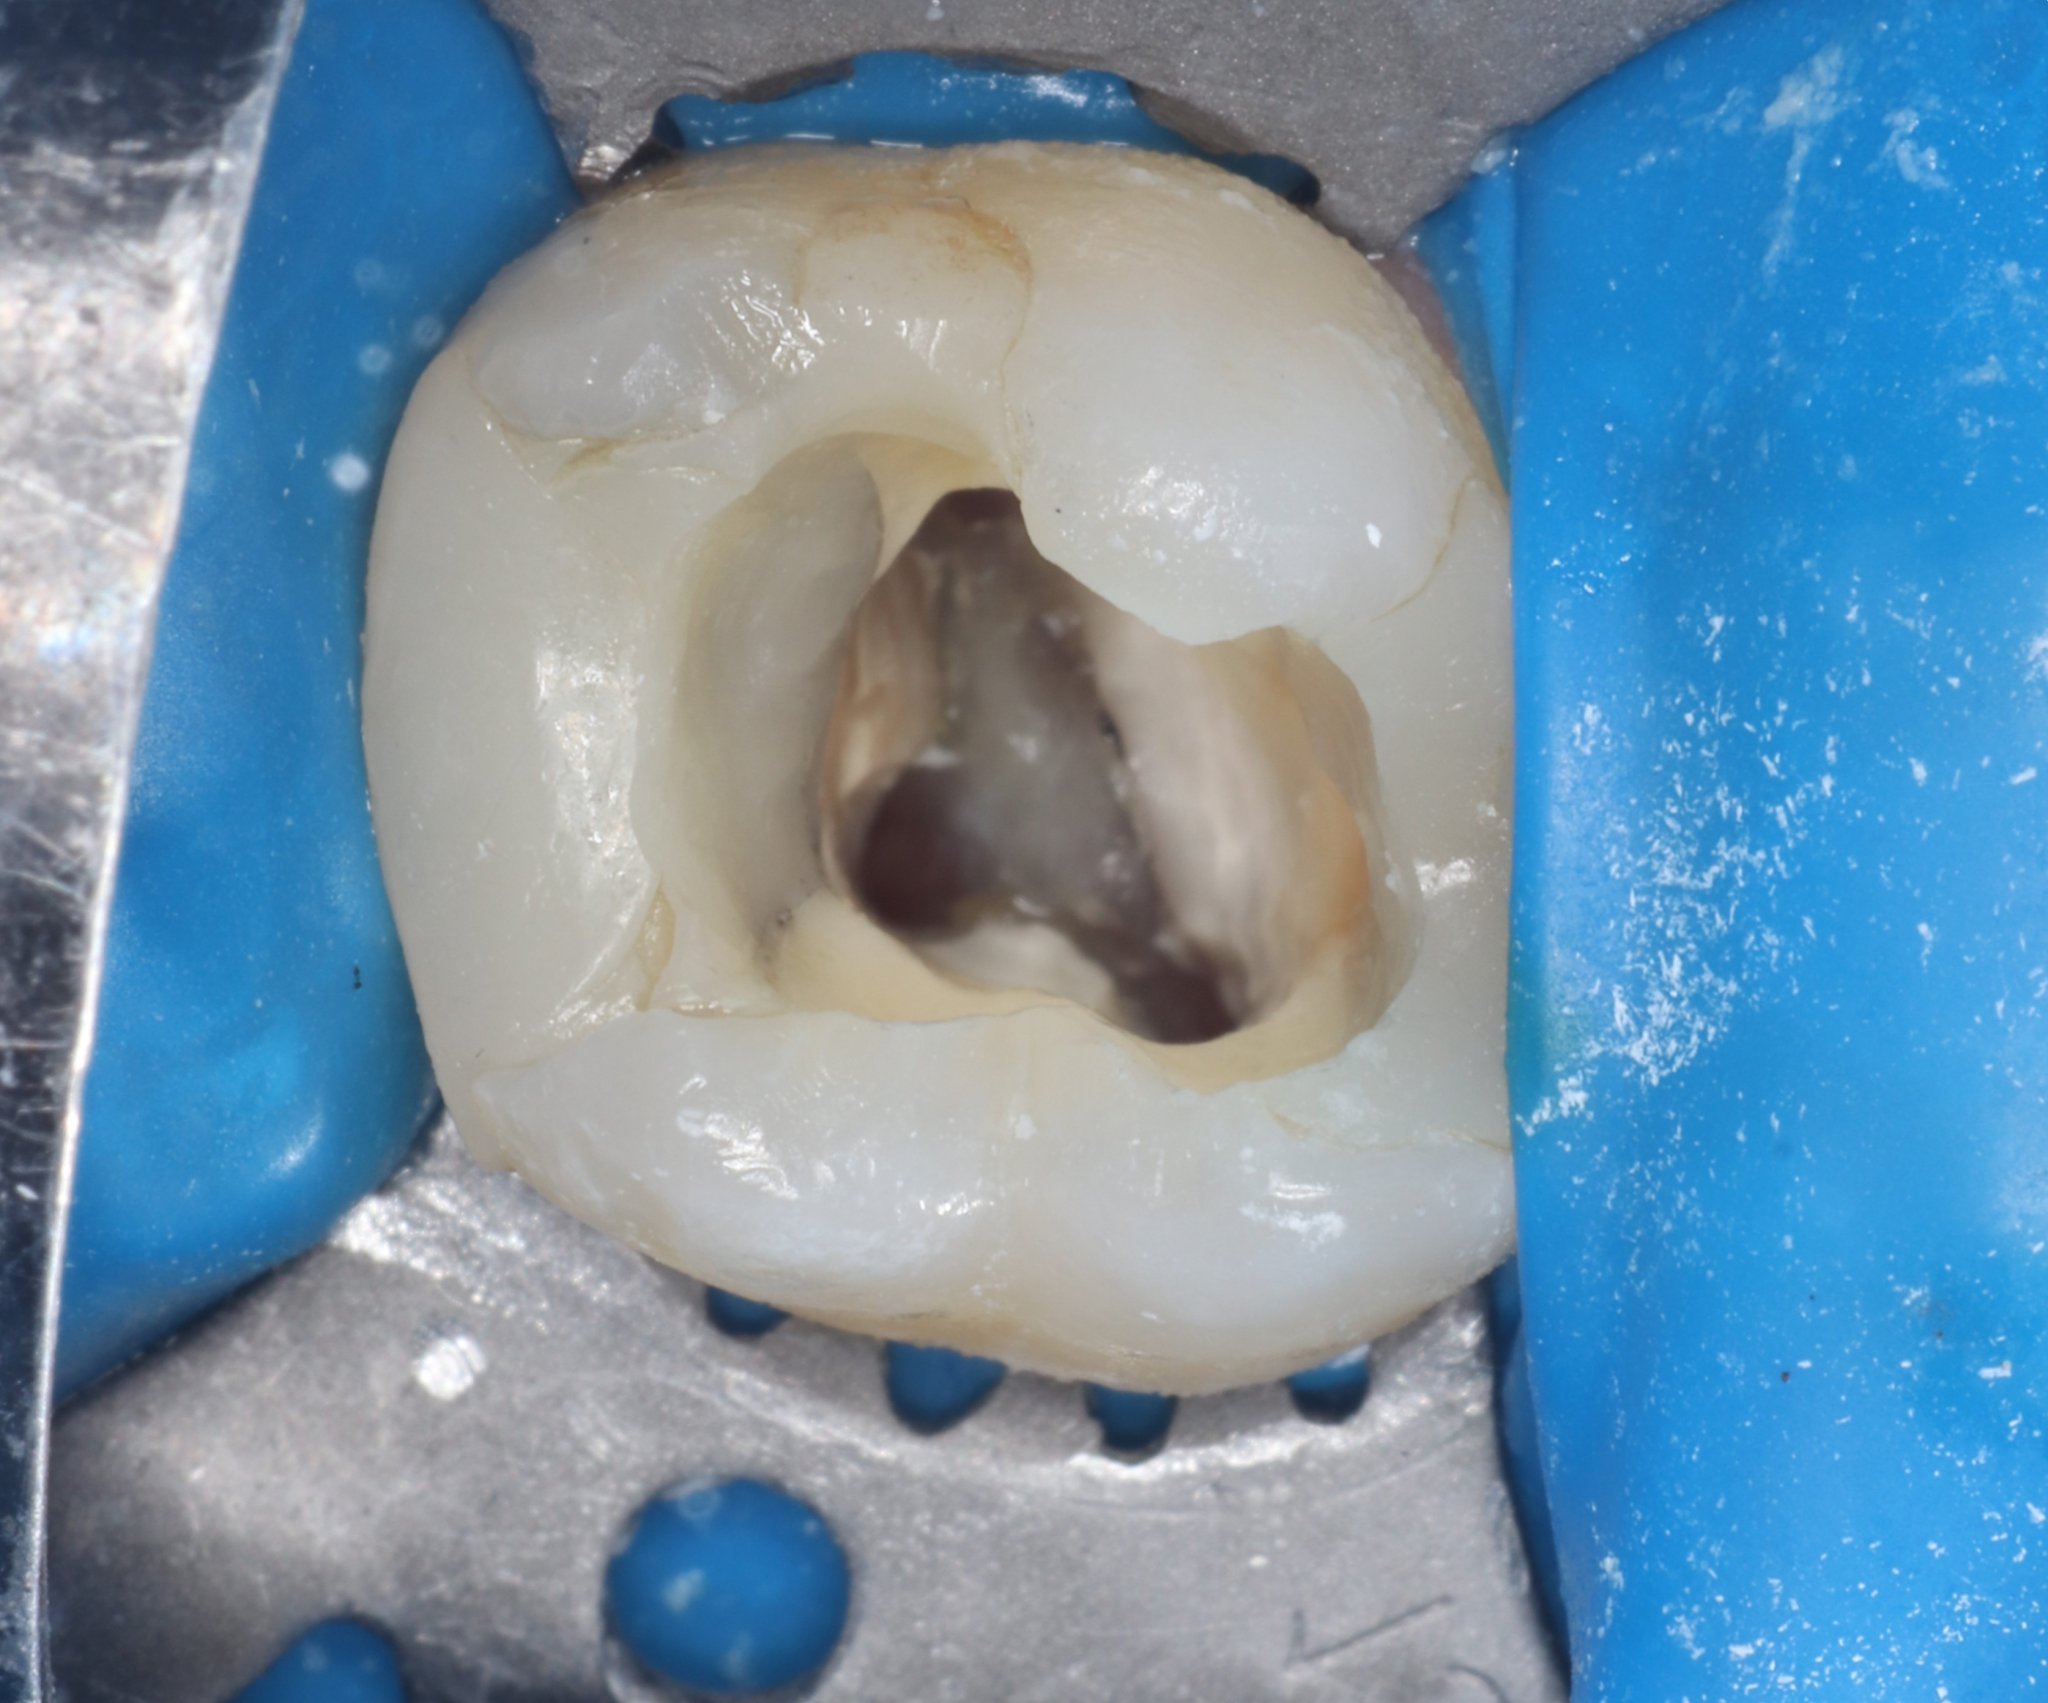

За мен оставането на зъб отворен много рядко е разумно решение, дори за временен зъб. когато се остави един зъб отворен в каналите му влиза всичко. Ето вижте на снимка колко горе долу са големи каналите. Това не е млечен зъб, но при едно дете на 6 години, каналите на четвъртите и петите зъби никак не са малки също.Когато освен инфекцията в каналите-вътре започне да влиза храна, плака, какво ли не става допълнителна инфекция-в каналите влизат и други микроби от устата. И така този подход е добър в краткосрочен план, ако зъболекарят е отворил хубаво каналите, вероятно почивката ви няма да се смути. Но вероятността този зъб да остане в устата ди 10-11 годишна възраст, когато трябва да се смени е съмнителна. Тоест това, което са направили краткосрочно е добре, дългосрочно не е.